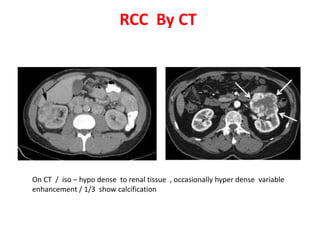

Von Hippel-Lindau disease is an autosomal dominant neurocutaneous disorder characterized by a high incidence of cysts in multiple organs and tumor development. Common manifestations include renal cell carcinoma in 25-40% of cases, cerebellar hemangioblastoma, retinal angioma, pancreatic cysts and tumors, and pheochromocytoma. Imaging findings include lesions that are intermediate to high signal on MRI and variably enhancing on CT and IVU.